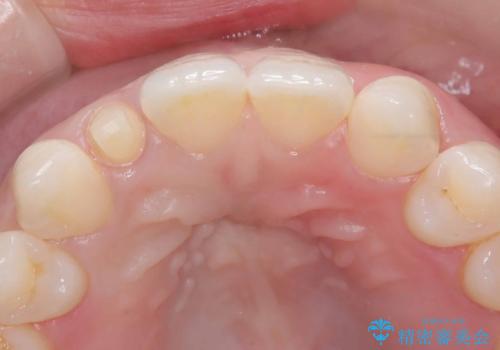

- 「前歯の見た目が気になる」を主訴に来院された患者様です。

右上2が矮小歯だったので、オールセラミッククラウンで審美修復しました。